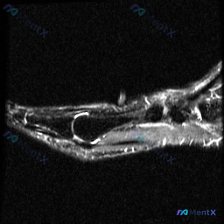

踝关节MRI读片病例分享,整理了完整分析思路 这是一例踝关节矢状位T2加权MRI,我把影像发现和分析思路整理出来,和大家一起讨论。 一、基本影像信息 这是踝关节MRI T2序列矢状位图像,可观察到胫骨远端、距骨、跟骨及周围软组织结构,核心阳性征象如下: 1. 骨骼关节改变:距骨穹窿(圆顶)可见明确局...